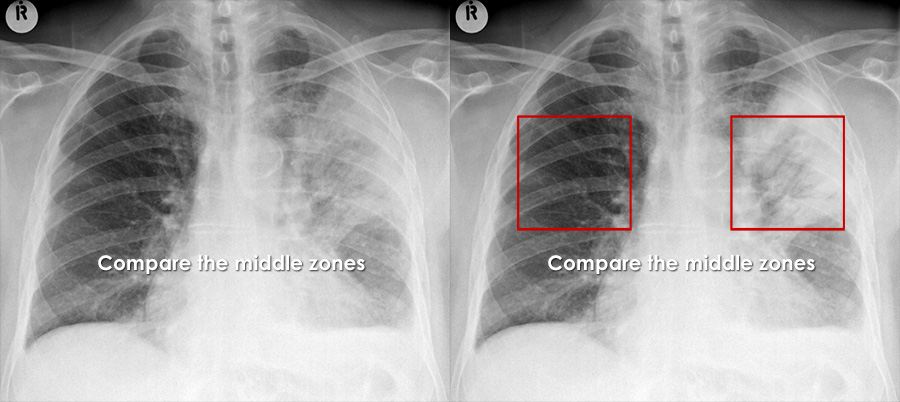

Double Pneumonia: Understanding and Managing the Condition

What is it? Pneumonia is an infection of the lungs, an invasion of lower respiratory tract by microrganisms that can cause a disease that ranges from mild to life-threatening. Worldwide, pneumonia kills more people than any other infectious disease, more than 4 million people a year, half of them under 5 years old.Although anyone can get pneumonia, […]